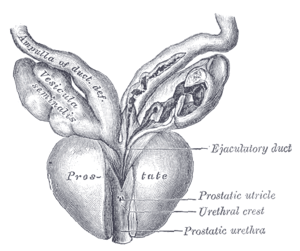

Vertical section of bladder, penis, and urethra. Dissection of prostate showing prostatic urethra.

Dissection of prostate showing prostatic urethra.